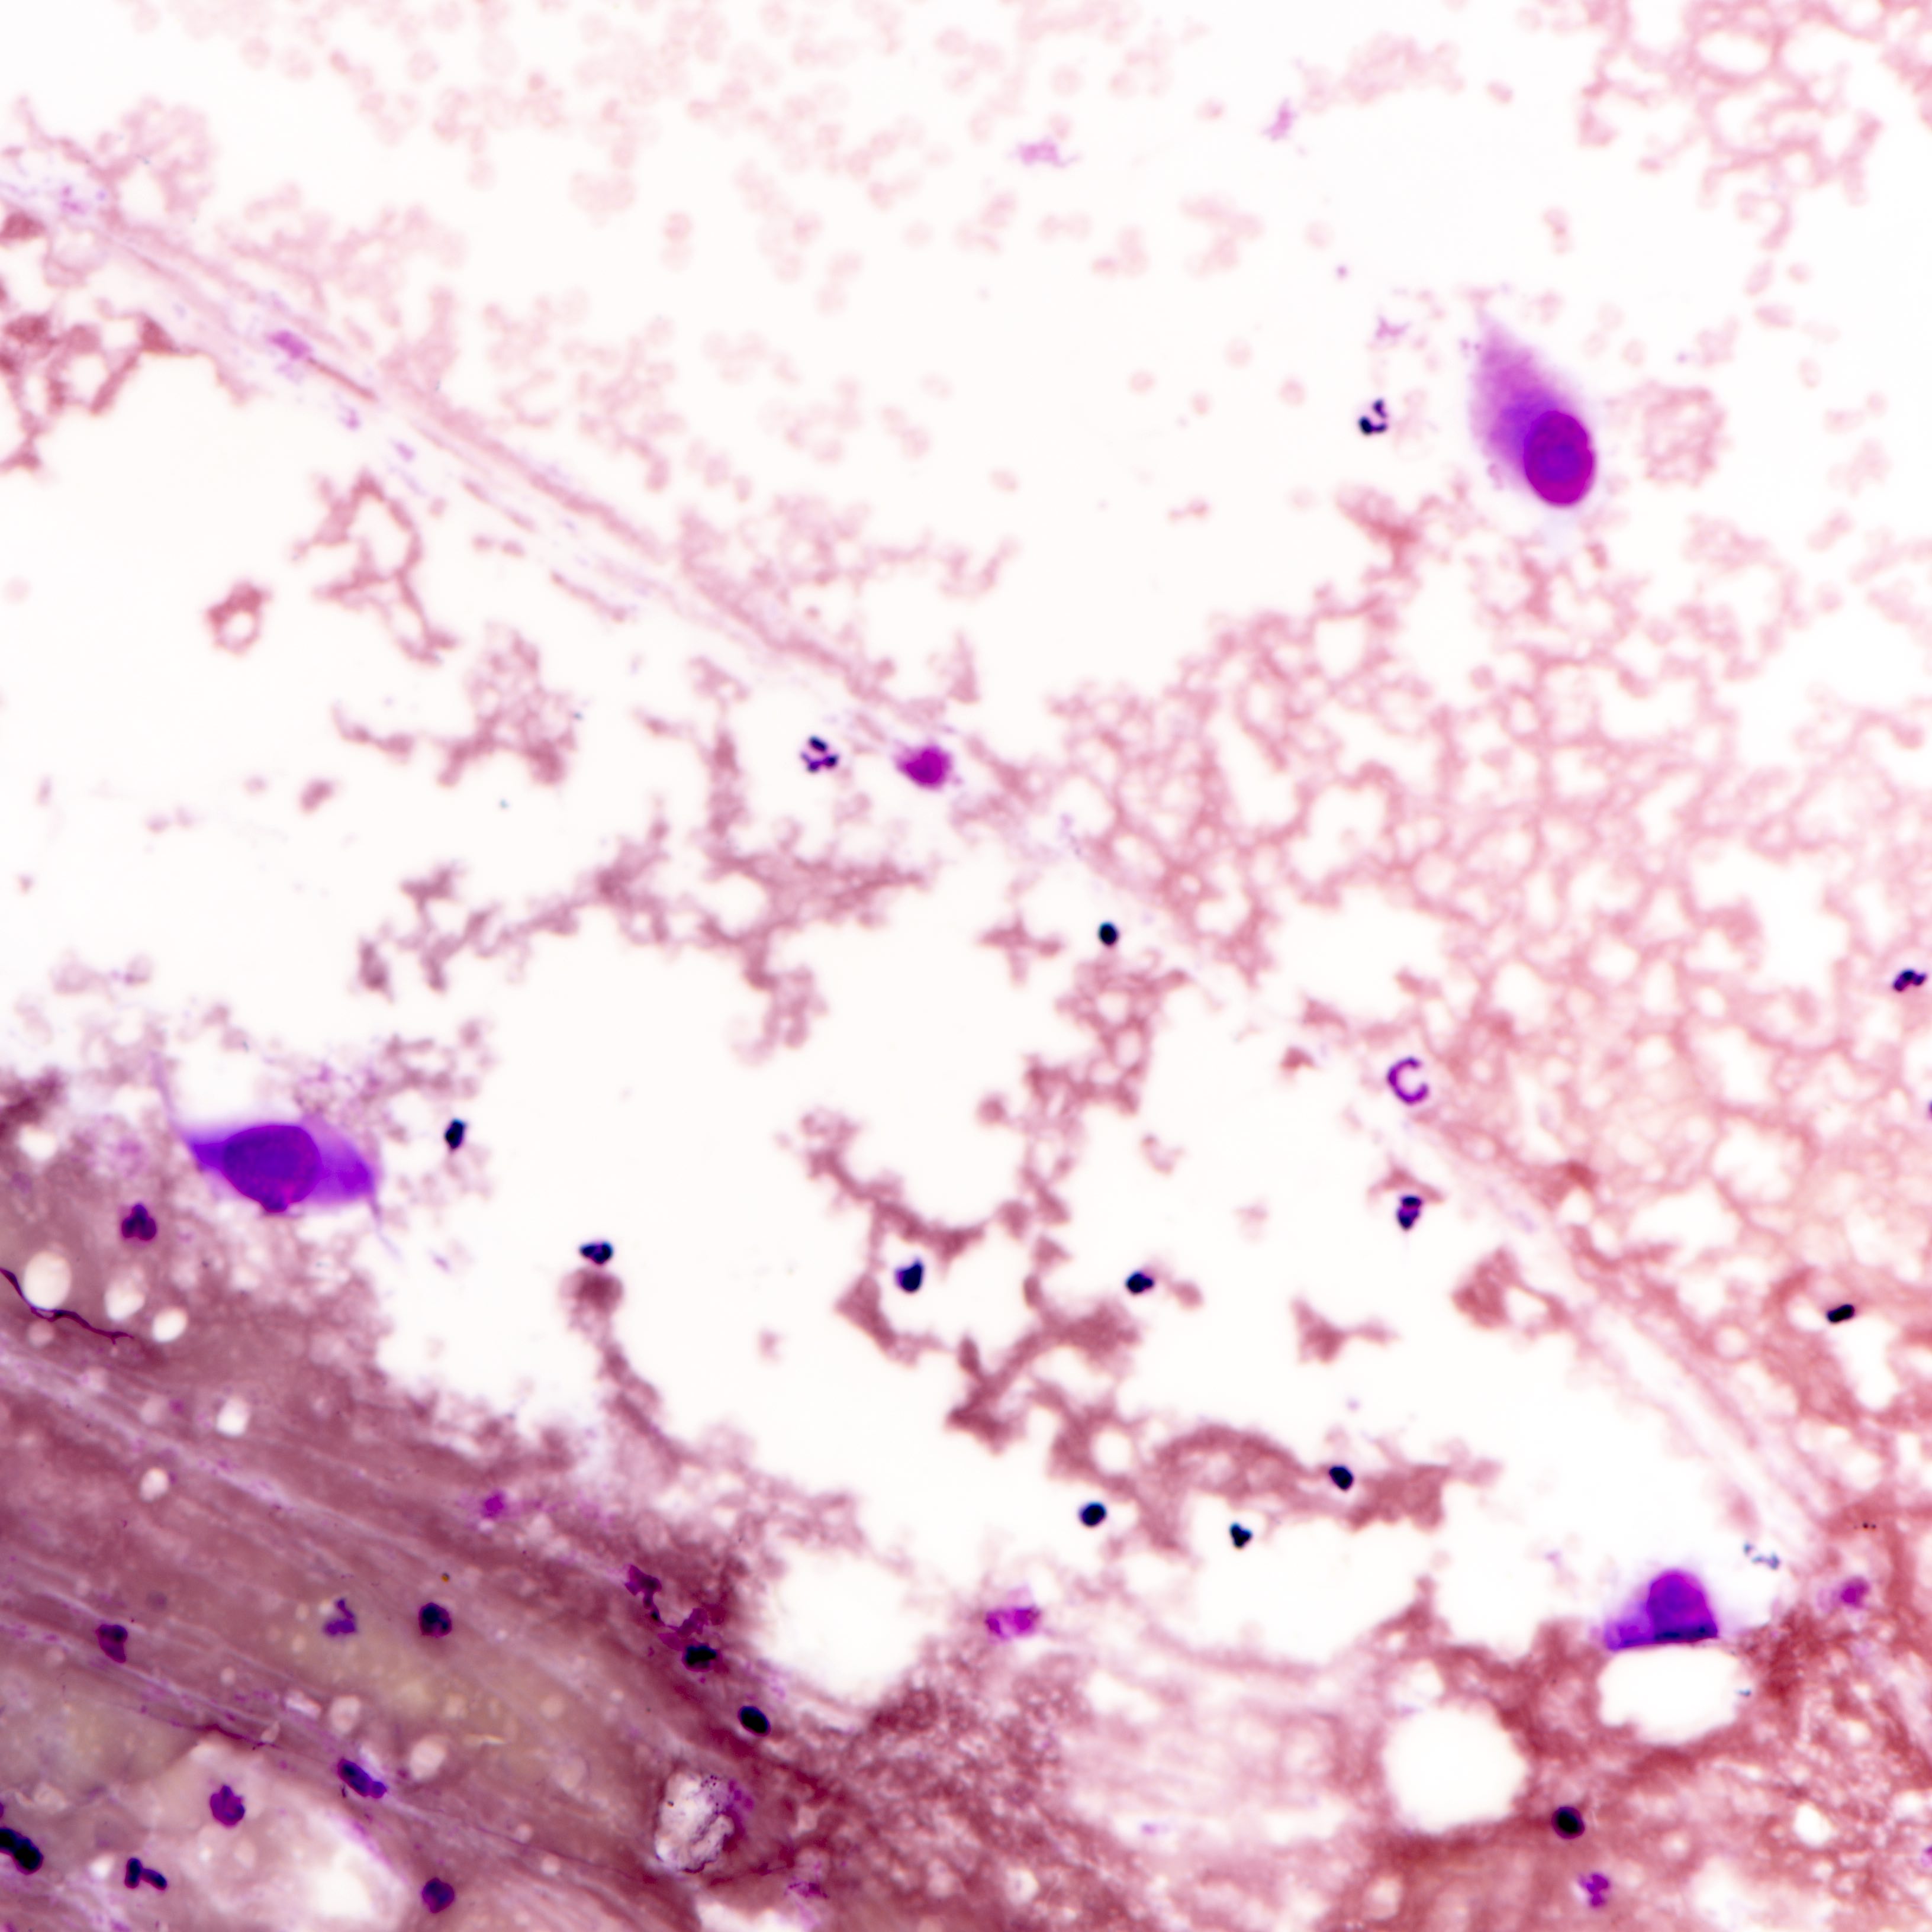

Cytology description

- Fibromyxoid stromal clumps

- Reduced epithelial stromal ratio compared with fibroadenomas

- Higher nuclear atypia and cellularity in phyllodes tumor of higher grades

- Large wavy and folded epithelial clusters

- Usually exhibits benign cytomorphology

- Occasionally, hyperplastic changes with enlarged and vesicular nuclei and small visible nucleoli may be seen

- Fibroblastic pavements

- Increased atypia in dispersed cells in phyllodes tumor of higher grades (Cancer Cytopathol 2010;118:33)

- Multinucleated tumor cells and marked stromal anaplasia reported in malignant phyllodes tumor (Cancer Cytopathol 2010;118:33)

Cytology images

Contributed by Joshua J.X. Li, M.B.Ch.B. and Gary M. Tse, M.B.B.S.

Malignant phyllodes tumor